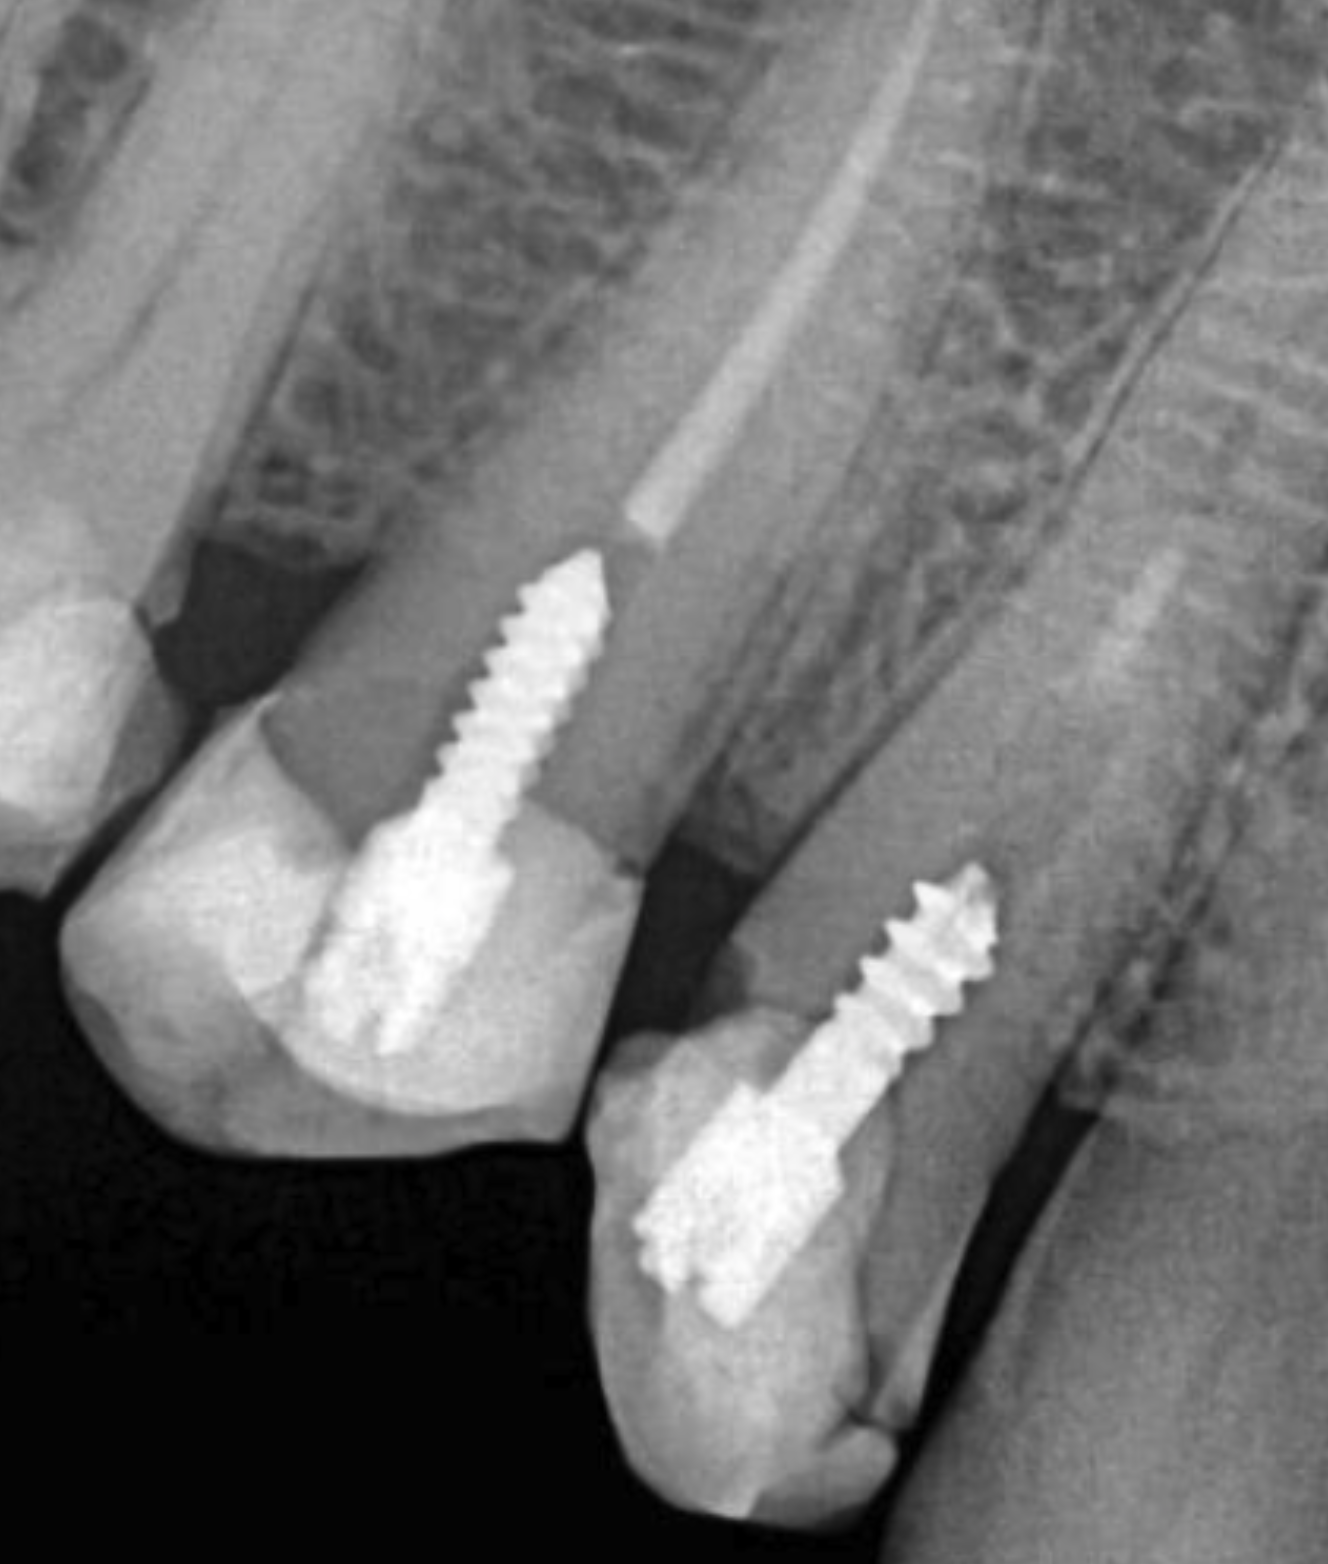

2. Sedación y colocación de implantes

Bajo sedación consciente, no sentirás nada. Colocamos los implantes de titanio con cirugía guiada por ordenador. Máxima precisión, mínima invasión.

Es más común de lo que crees y tenemos solución para prácticamente todos los casos. Técnicas como los implantes zigomáticos o la elevación de seno permiten colocar implantes incluso con pérdida ósea severa. En tu TAC gratuito evaluamos tu caso concreto y te explicamos las opciones reales, sin obligación.

Los implantes de titanio premium que utilizamos (Straumann y Nobel Biocare) tienen una vida útil superior a 25 años, y en la mayoría de casos duran toda la vida. Por eso ofrecemos garantía vitalicia en el implante. La prótesis puede necesitar ajustes o reemplazo a los 15-20 años, pero el implante en sí es para siempre.